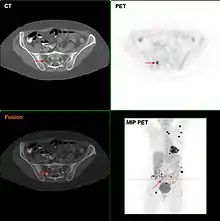

F18-FDG PET/CT in a melanoma patient showing multiple lesions, most likely metastases

Metastatic melanomas can be detected by X-rays, CT scans, MRIs, PET and PET/CTs, ultrasound, LDH testing and photoacoustic detection.[85] However, there is lack of evidence in the accuracy of staging of people with melanoma with various imaging methods.[86]

It is common for patients diagnosed with melanoma to have chest X-rays and an LDH test, and in some cases CT, MRI, PET, and/or PET/CT scans. Although controversial, sentinel lymph node biopsies and examination of the lymph nodes are also performed in patients to assess spread to the lymph nodes. A diagnosis of melanoma is supported by the presence of the S-100 protein marker.